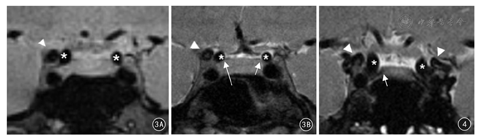

冠状位3D-SPACE-T2WI、HR-DIR-T2WI显示同层面DDR图像(图3):两种扫描序列均能显示出DDR内外缘,前床突及鞍隔的硬膜延续与颈内动脉床突段之间,分别形成DDR外侧隔及内侧隔。3D-SPACE- T2WI序列能较为直观的观察DDR结构,但硬膜隔结构显示边缘模糊(图3A)。HR-DIR-T2WI序列显示硬膜隔更为清晰锐利,右侧DDR内侧隔与颈内动脉床突段管壁紧密连接,并见内侧隔形成小凹样结构,即颈动脉窝(图3B及图4)。

20例(40侧)志愿者中,3D-SPACE-T2WI序列上,观察到颈动脉窝23侧,其中B型16侧、C型7侧;颈动脉窝深度1.0~7.5 mm,平均(2.07±1.31)mm。HR-DIR-T2WI序列上,观察到颈动脉窝19侧,其中B型13侧、C型6侧;颈动脉窝深度1.1~7.5 mm,平均(2.13 ±1.33)mm。结果显示,颈动脉窝区结构细小且模糊,HR-DIR-T2WI序列对于颈动脉窝的显示更为清晰,增加了分型及测量的准确性;两种序列颈动脉窝深度比较,差异无统计学意义(t=0.144, P>0.05)。